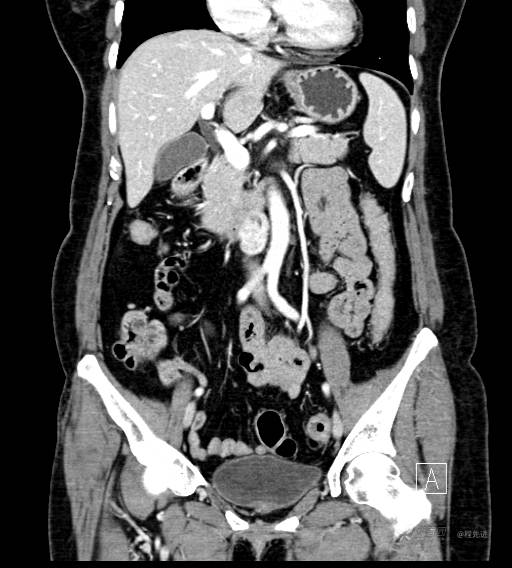

CT增强门脉期

CT增强静脉期

CT增强冠状位重建